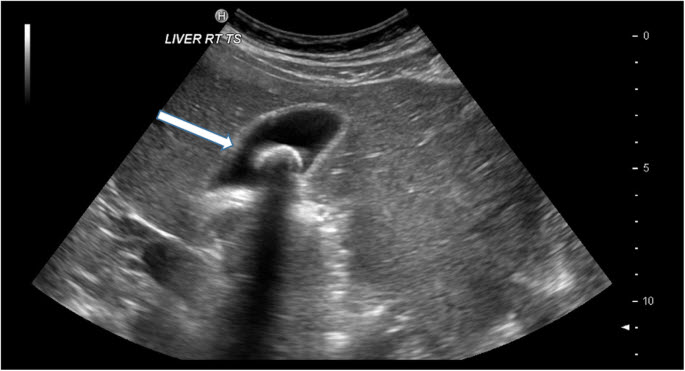

담석증 검사-복부 초음파 검사-담석은 CT나 X레이로도 확인하기 어려운 경우가 많으며, 1차 검사는 복부 초음파 검사입니다.

담석의 복부 에코 영상 초음파 소견에서 간과해서는 안 될 것은 음향 그림자(acoustic shadow)입니다.